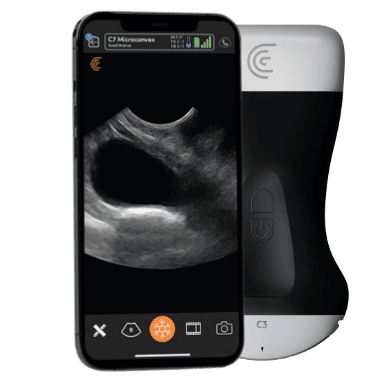

T-Mode es un enfoque innovador para la educación en ecografía diseñado para mejorar sus habilidades de escaneo utilizando la potencia de la inteligencia artificial en aplicaciones de Estética y Cirugía Plástica. Cette technologie novatrice superpose des couleurs distinctes, des motifs et des étiquettes pour identifier et différencier les structures anatomiques et les couches de tissu.